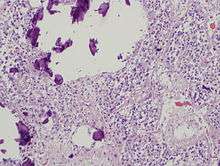

Pineal gland parenchyma with calcifications.

The pineal body consists in humans of a lobular parenchyma of pinealocytes surrounded by connective tissue spaces. The gland's surface is covered by a pial capsule.

The pineal gland consists mainly of pinealocytes, but four other cell types have been identified. As it is quite cellular (in relation to the cortex and white matter), it may be mistaken for a neoplasm.[14]